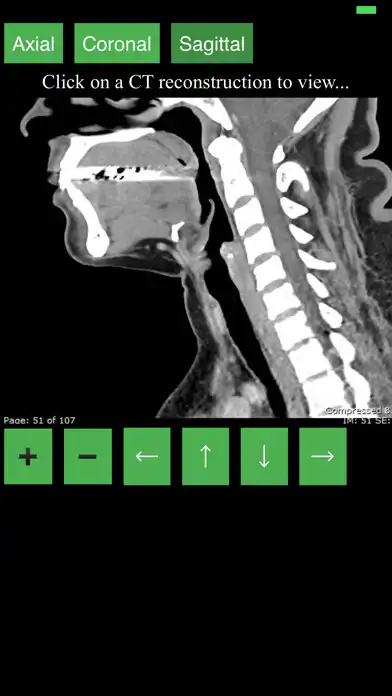

This app provides a dynamic and interactive method of viewing cross-sectional human anatomy on computed tomography (CT). The information contained in this app cannot be guaranteed for completeness and accuracy.

- Labeling of anatomical parts

- 3D Anatomic localization